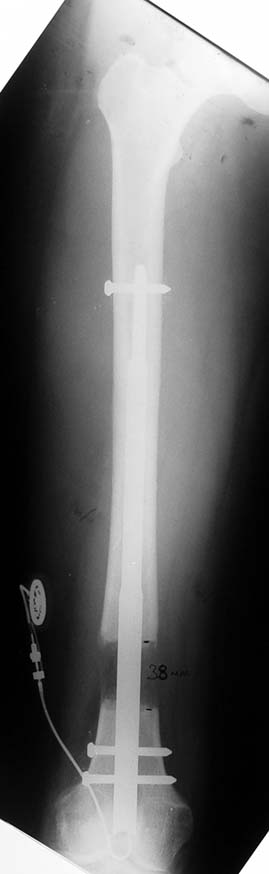

Case 2